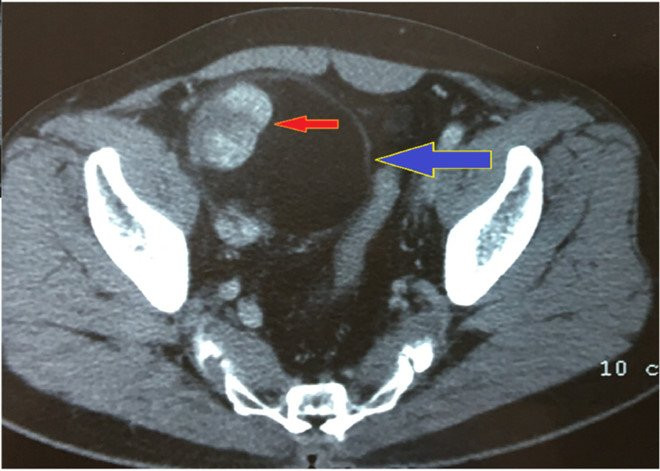

Hình ảnh CT scan của bệnh nhân được các bác sĩ xem và đánh giá ngay trong phòng mổ . (Ảnh: SYT cung cấp)